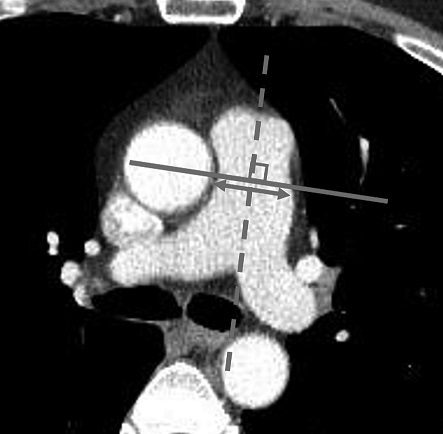

Haemoptysis is a common complication of lung biopsy, which can occasionally be very severe. This paper, based on a very large number of patients, evaluates the risk factors, among them the main pulmonary artery diameter (mPAD).

mPAD enlargement was a significant risk factor for severe PTNB-related haemoptysis.

mPAD can be useful in screening high-risk patients for severe haemoptysis.